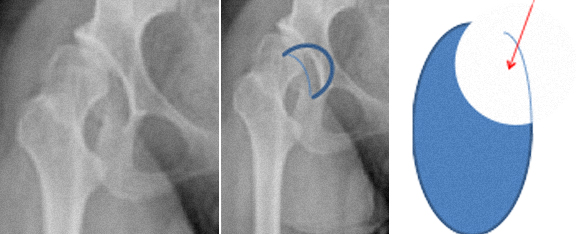

Na displasia da anca ou doença displásica da anca (DDA) o acetábulo é oblíquo, pouco profundo, estreito, lateralizado, antevertido e com deficiente cobertura anterosuperior.

O fémur tem cabeça pequena, colo curto, anteversão exagerada do colo, ângulo cervicofiafisário aumentado, desvio posterior do grande trocanter, canal femoral estreito.

As lesões do labrum são frequentes e as suas causas principais são o traumatismo, o conflito femoroacetabular, a laxidez capsular e a hipermobilidade, a displasia da anca, e podem ser também de natureza degenerativa.

A lesão do labrum tem início na junção condro-labral, geralmente há preservação da inserção óssea do labrum e este tipo de rotura é mais frequente no conflito tipo CAM.

A rotura também pode ser intrasubstância do labrum e este tipo de rotura é mais frequente no conflito tipo pincer.

O labrum pode estar degenerado, pode ter rotura parcial ou completa (de toda a espessura), pode estar destacado, pode estar ossificado ou calcificado, pode ter quistos.